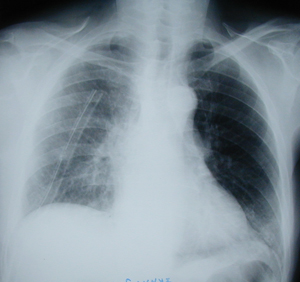

Εικόνα 4

Μετεγχειρητική οπισθιοπροσθία ακτινογραφία θώρακος μετά από δεξιά άνω λοβεκτομή, όπου παρατηρείται πλήρης έκπτυξη του κάτω και του μέσου λοβού.

Διακρίνεται ο σωλήνας παροχέτευσης του θώρακος.